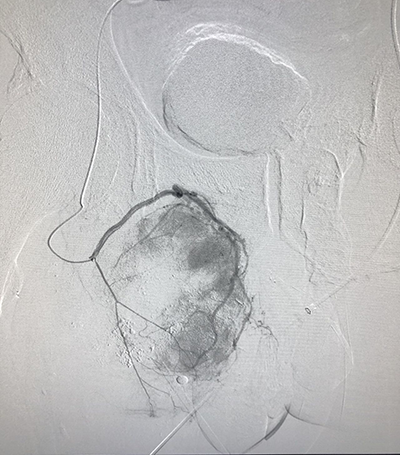

(介入術(shù)中操作)(肝癌的介入治療)

(肺癌的介入治療)(盆腔惡性腫瘤的介入治療)

(腦腫瘤的介入治療)(子宮肌瘤的介入治療)